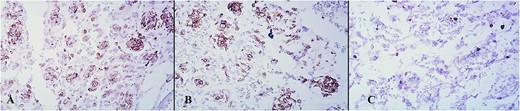

On immunohistochemical staining, tumor cells were positive on Vimentin, Smooth Muscle Actin (SMA), and focally on CD34. They stained negative on Desmin, Caldesmon, CD31, HMB 45, GFAP, CKAE1/AE3, CK7, EMA, S100, CD99, and p63. The tumor’s proliferation index after staining with Ki-67 was ~5% (Fig. 6a–c).

Small capillaries lined by relatively monomorphous round cells, with mild pleomorphism and sparse mitotic activity, surrounded by myxoid stroma (HeEo, ×100).